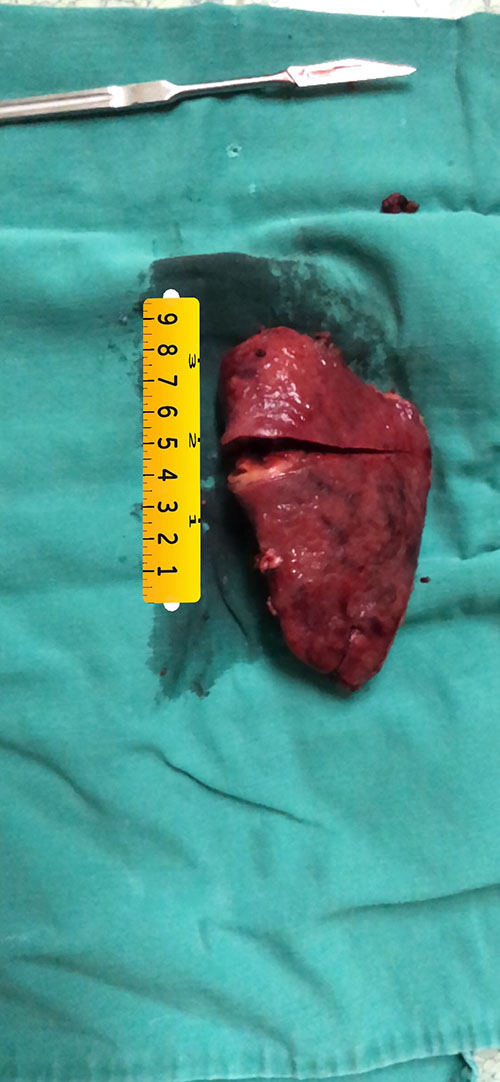

S6肝癌-腹腔镜S6切除